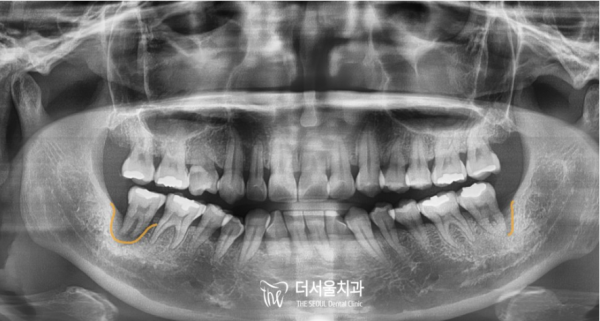

8개월의 시간이 후른뒤에 환자분의 왼쪽 아래 어금니 역시 저희 태평역치과 더서울치과에 찾아오셔서

치료가 진행되었으며, 역시 디지털 임플란트 방식으로 안전하고 정확하게 심어졌습니다.

After 8 months, your lower left molar also came to Taepyeong Station Dental Clinic, The Seoul Dental Clinic

Treatment has progressed and was also safely and accurately planted with digital implants.

양쪽 아래 어금니가 모두 예쁘게 잘 심어진 것을 확인할 수 있습니다.

환자분께서는 저희 태평역치과 더서울치과의 디지털임플란트에 크게 만족하신 치료였습니다.

보신것 처럼 저희 더서울치과의 디지털임플란트는 적절한 위치에 임플란트의 픽스처를 잘 심을 수 있도록

컴퓨터를 통해 정확한 위치의 가이드라인을 제시해주기 때문에 안전하고 정확한 임플란트 식립이 가능하다는 장점이 있습니다.

You can see that both lower molars are beautifully planted.

The patient was very satisfied with the digital implant of Taepyeong Station Dental Clinic The Seoul Dental Clinic.

As you can see, the digital implants of The Seoul Dental Clinic help you plant the fixture of the implants in the right place

It has the advantage of being able to implant safely and accurately because it provides accurate location guidelines through a computer.